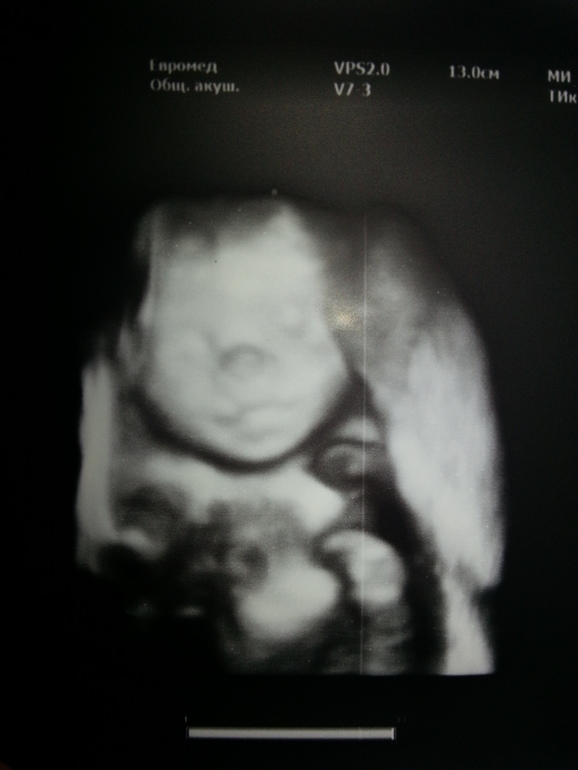

НЕ ПЕРВЫЙ малышСегодня мы были на узи в Евромеде у Харченко НВ. Очень внимательный толковый специалист!Все рассказала,показала :)

Все у малышки хорошо:) Головной мозг развит правильно, с сердечком все хорошо, чс 157 ударов, мозжесок, желудок, кишечник все показали и все в порядке:) Отдельно спросила про почки. Все с ними хорошо, все прекрасно :)))))Спросила почему интересуюсь. Объяснила. Ее ответ: "Так они,наверное,мальчики?". Удивила,угадала. Говорит,что часто у мальчиков проблемы с почками из за уретры.

Деееееевоооочкааааа!!!!!)))))))

Показала нам половые губы и клитор:)))Мы правда ничего не поняли:))))Сднлала фото для рассмотрения!:) хи хи